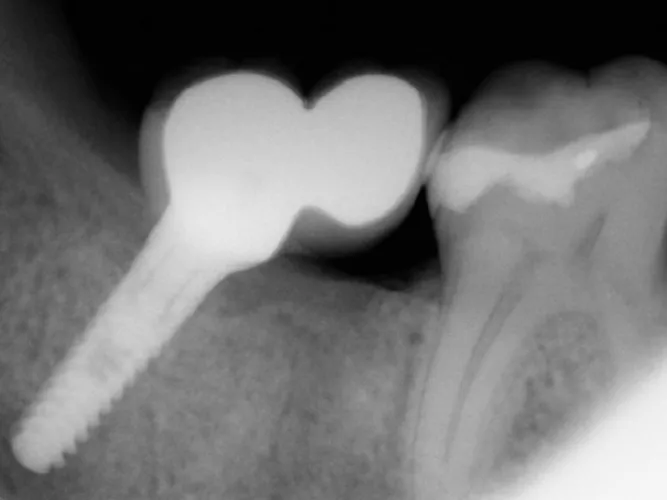

Dental implant bridges are a durable, long-lasting option for patients missing several teeth in a row. Unlike traditional bridges that rely on adjacent natural teeth for support, implant bridges are anchored securely to dental implants placed directly into the jawbone. This provides superior stability, preserves bone structure, and helps maintain your natural facial shape.

Each implant bridge is custom-crafted to match the color, size, and shape of your natural teeth, offering a seamless and aesthetic result. With implant bridges, you can enjoy a comfortable, secure bite and improved speech—without the worry of slipping or the need for adhesives.

This treatment is ideal for patients seeking a fixed, non-removable alternative to partial dentures, with the added benefit of protecting long-term oral health.